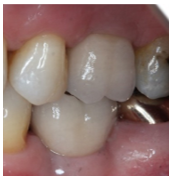

From Left to right; 1. Radiograph of placed implant with healing abutment. 2. Photograph of healed gingiva 10-weeks post-op. 3. Radiograph 1-year post-op. 4. Photograph 1-year post op of restored implant.

Patient presented 10-weeks after the implant placement, proper osseointegration was confirmed and the fixture was restored by a specialist Prosthodontist. At the 1-year supportive periodontal appointment, a diagnosis of healthy peri-implant tissues was confirmed (Figure 3 and 4).